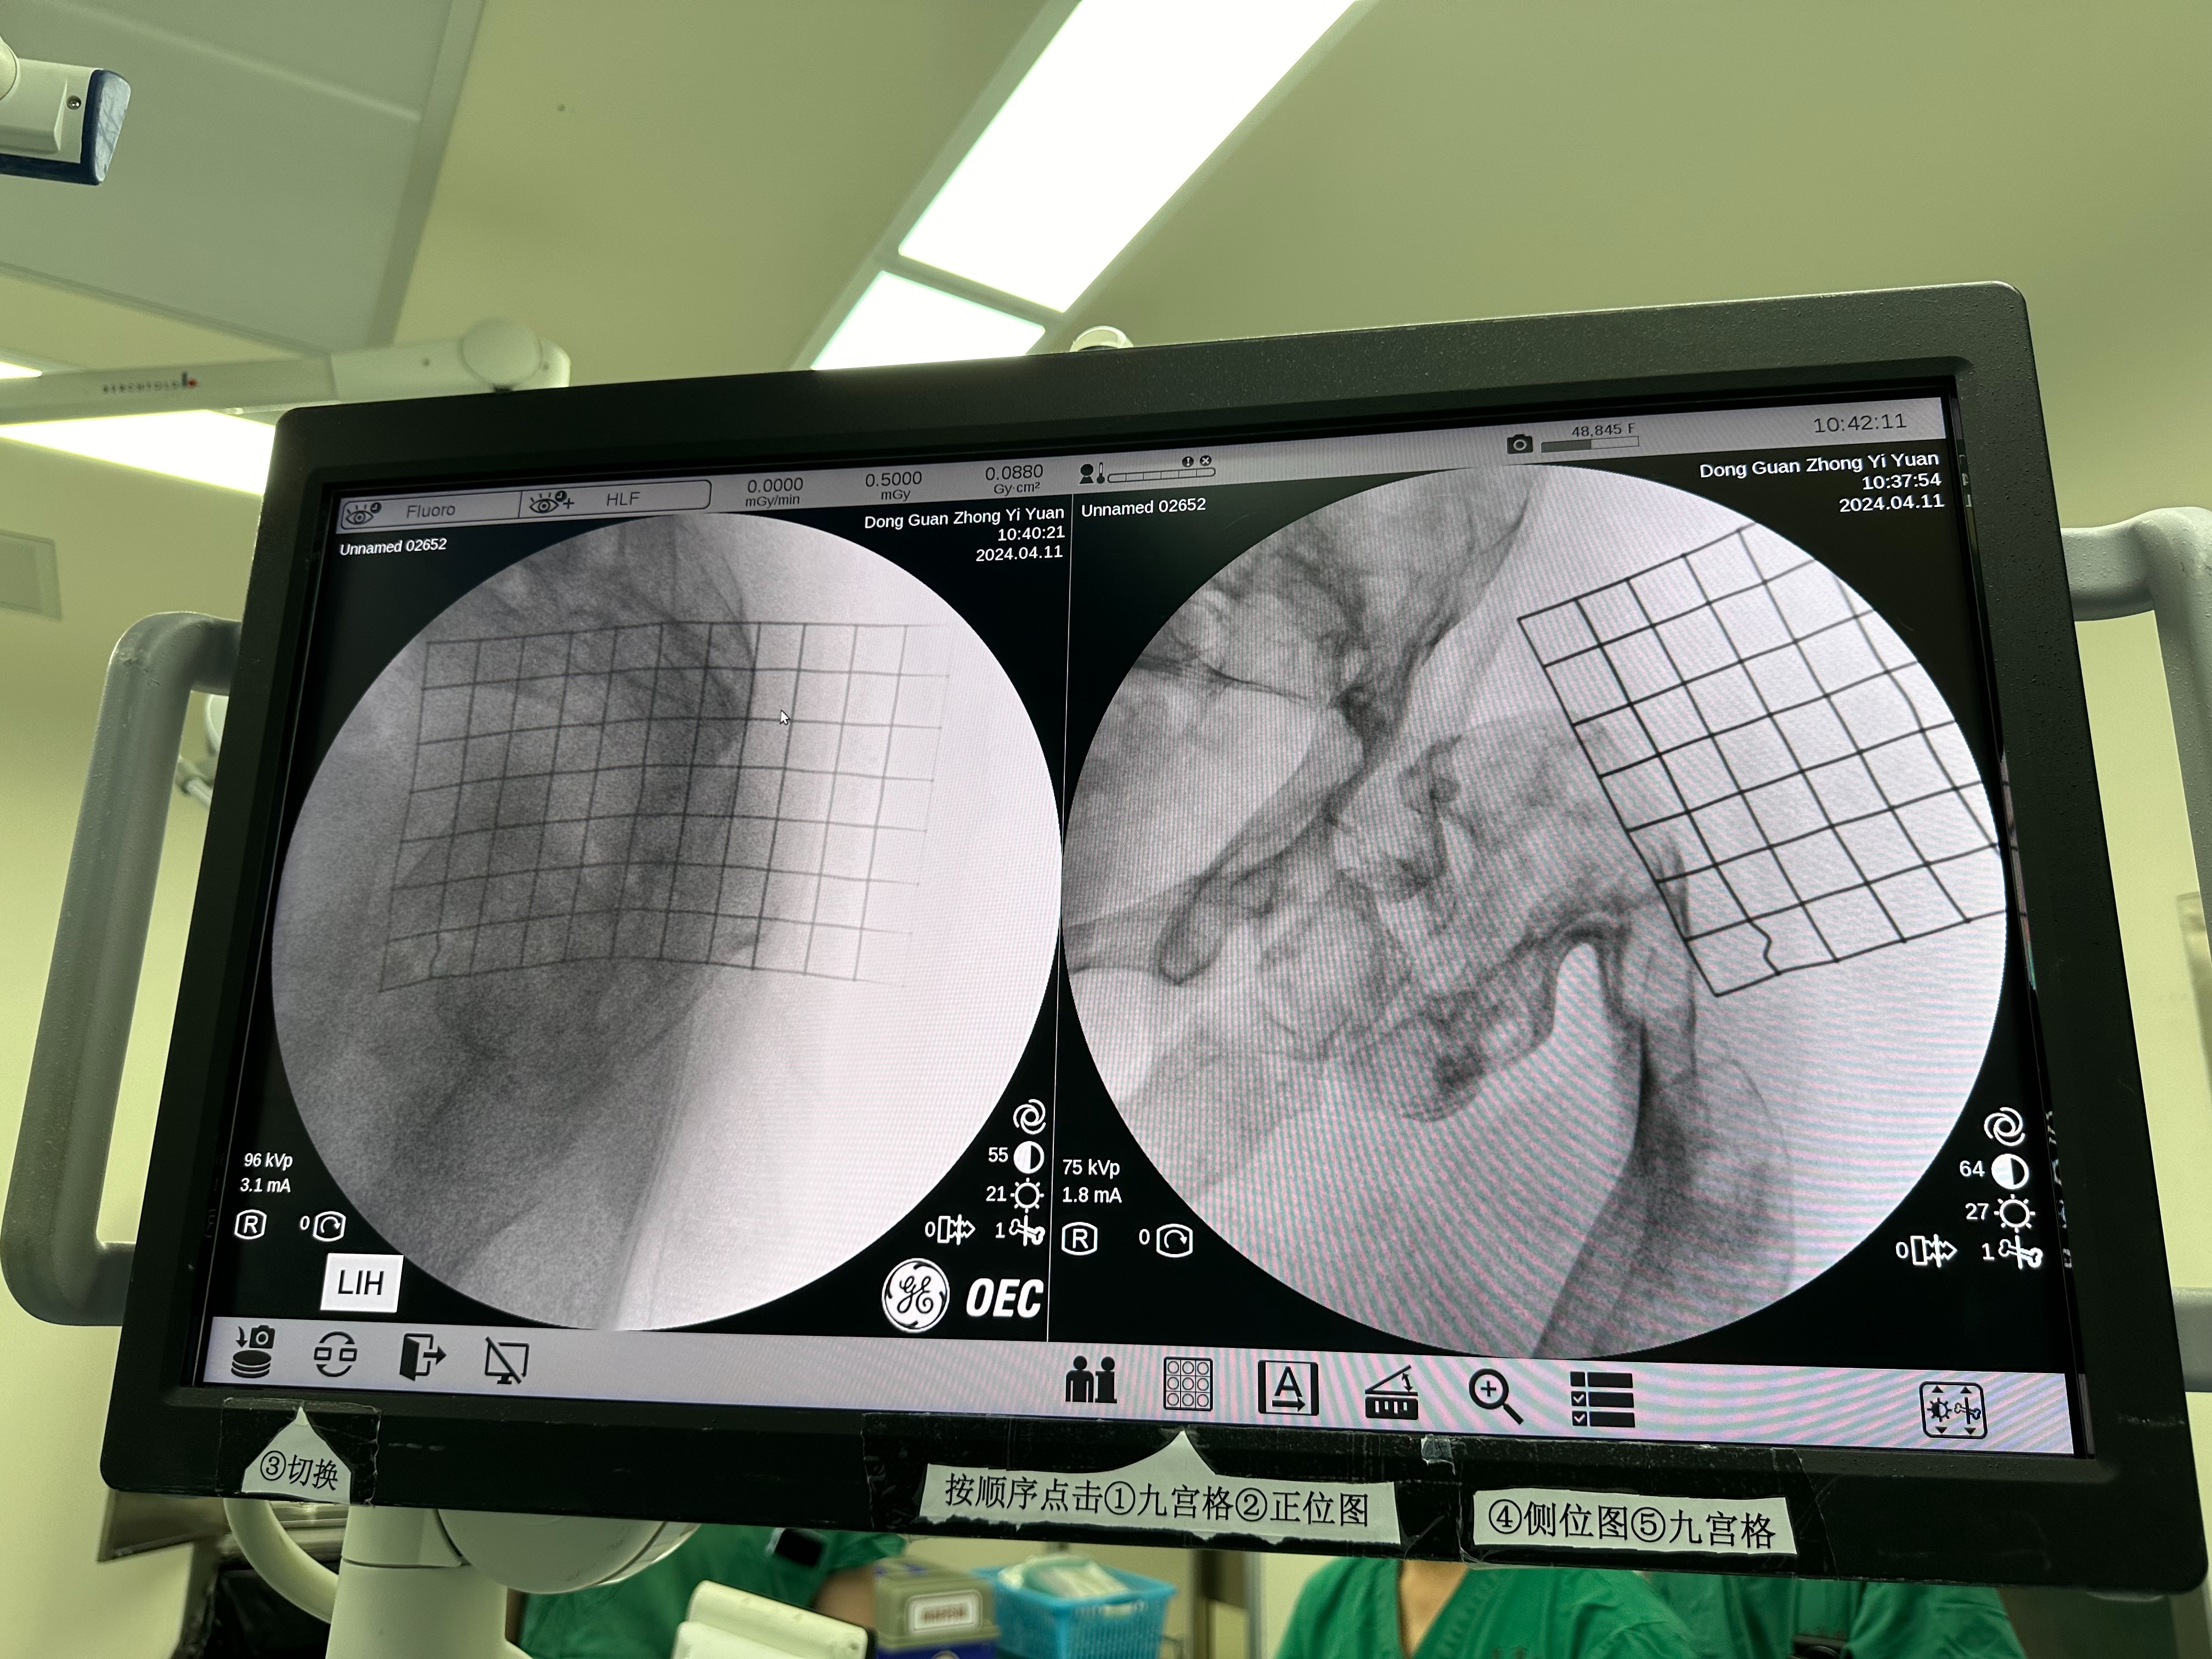

In the morning of April 11th, Prof. Freude performed an intramedullary nail fixation with Director LIANG's team. This surgery is medical treatment for a patient with proximal femur fracture due to osteofibrous dysplasia, and the surgical plan and physical examination were discussed for the patient yesterday.

There was already severe s-shaped deformity in the patient's femur and the cortex of the femur was in minimal quality, and this made both intra-operative imaging to check nail entry and placing of intramedullary nails extremely challenging.

During pre-op preparations, Prof. Freude, together with Director LIANG and Director WU Xiankui, measured the position of the greater trochanter using a mesh and identified the nail entry point.

During the operation, Prof. Freude and Director WU worked together to place the intramedullary nails and discussed with Director LIANG about the solutions while there were difficulties in drilling the nails into the fracture. Finally, the femoral fracture was fixed by three elastic femoral intramedullary nails and the operation was successfully accomplished.